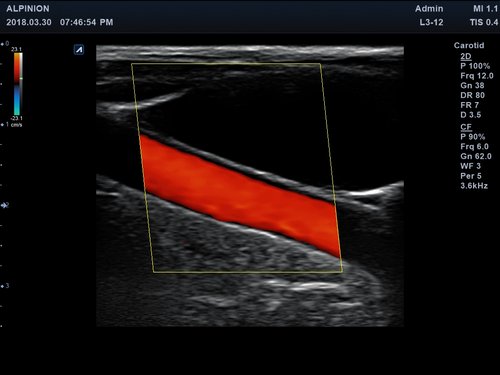

Anwendungsbereiche Abdomen MSK, Nerven, Karotis, periphere Gefäße, Schilddrüse, Mamma

Bildgebungs-Modi B-Modus, CF, M, PW, PD B-Modus, CF, M, PW, PD

• Farbdoppler: farbige Darstellung der Richtung des Blutflusses